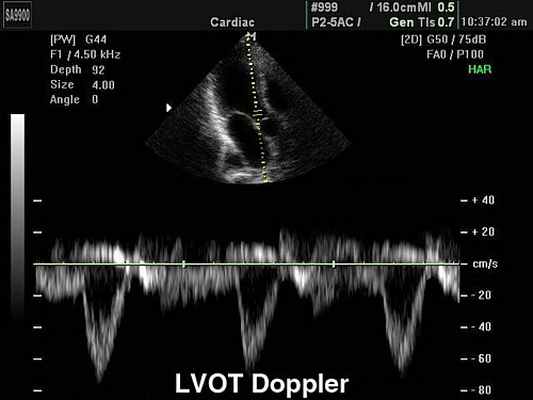

Допплер-эхокардиография аорты и аортального клапана

1. При наличии препятствия току крови в выходном тракте левого желудочка или аорте возникает увеличение скорости систолического потока выше места сужения более 1,5 м/с.

2. Проводится оценка величины градиента обструкции по уравнению Bernoulli (табл. 11).

3. Расчет поперечного сечения аорты по формуле Kevin.W:

AVA = p * (D/2) 2 * V1 / V2

где: AVA - поперечное сечение аорты на уровне аортального клапана,

D - диаметр выходного тракта левого желудочка по данным 2-х мерной эхоКГ,

V1 - пиковый систолический поток в выходном тракте левого желудочка,

V2 - пиковый систолический поток в восходящей аорте.

4. Оценка систолической функции левого желудочка.

MOK = Vcp * S * E * ЧСС

где: МОК - минутный объем кровообращения (мл/мин),Vср - средняя скорость потока в выходном тракте ЛЖ в систолу (см/с), S - поперечное сечение выходного тракта (см 2 ), Е - период изгнания (с),ЧСС - частота сердечных сокращений.